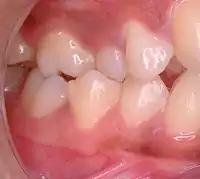

Malocclusion in 10-year-old girl

Class I with severe crowding and labially erupted canines